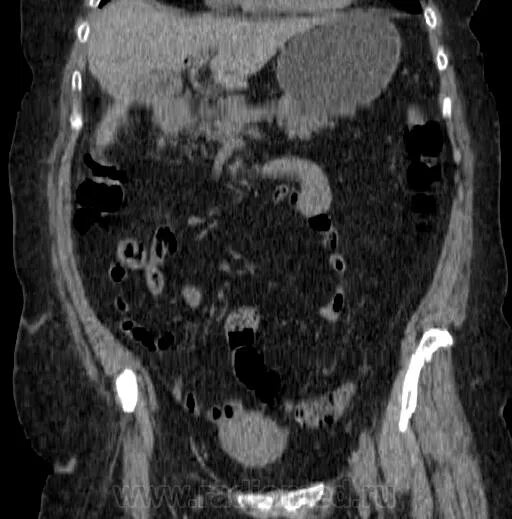

Заболевание кт